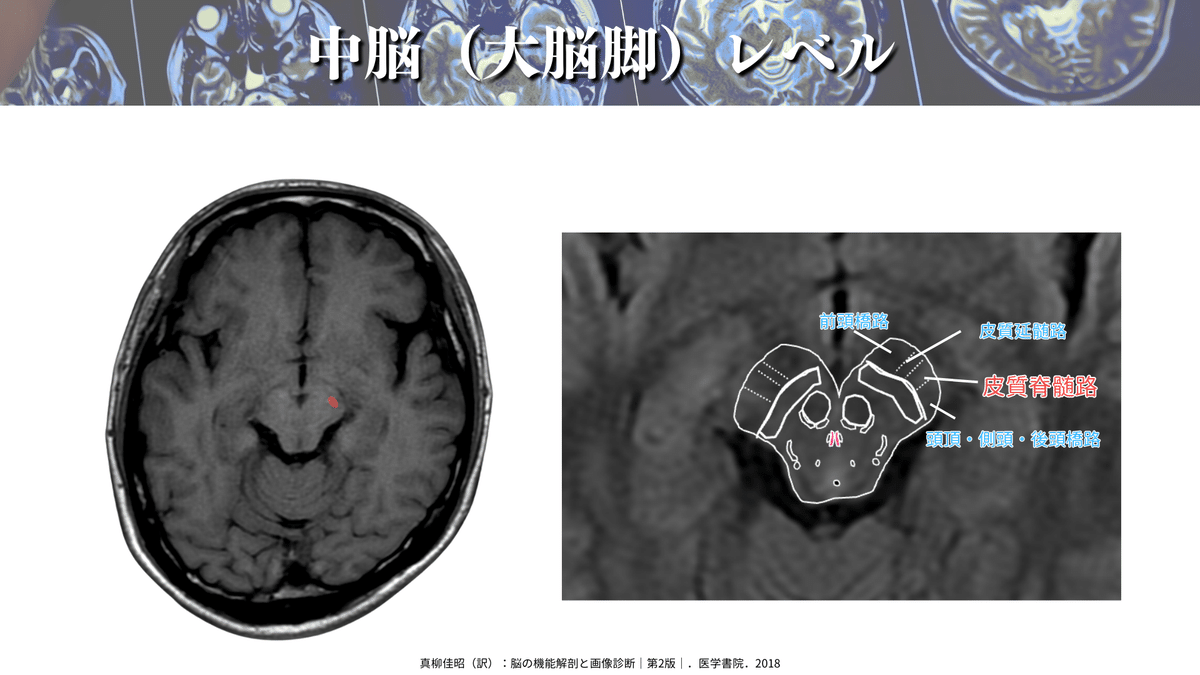

さて、本題に戻りまして、解像度を上げてみるとこんな感じです!

CSTは大脳脚というところを通過していきます🏃♀️

大脳脚も詳しくみると大きく3ブロックになっていまして、内側が前頭橋路、中間が皮質延髄路とCST、外側が頭頂・側頭・後頭橋路が通るようです😳

DTTで確認をしても同様の場所を通過していますね👍(下図)

なので大脳脚では真ん中あたりを通っていると覚えると良いかもしれません☝️